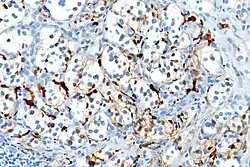

With immunohistochemistry, the chief cells located in the cell balls are positive for chromogranin, synaptophysin, neuron specific enolase, serotonin, neurofilament and Neural cell adhesion molecule; they are S-100 protein negative. The sustentacular cells are S-100 positive and focally positive for glial fibrillary acidic protein. By histochemistry, the paraganglioma cells are argyrophilic, periodic acid Schiff negative, mucicarmine negative, and argentaffin negative.

S100 immunostain highlighting the sustentacular cells in a paraganglioma

S100 immunostain highlighting the sustentacular cells in a paraganglioma -